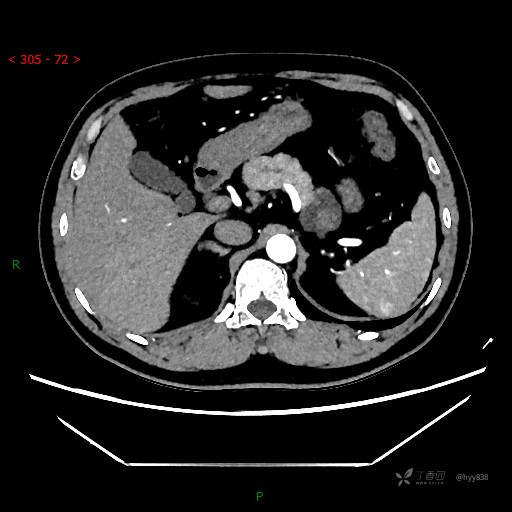

静脉期